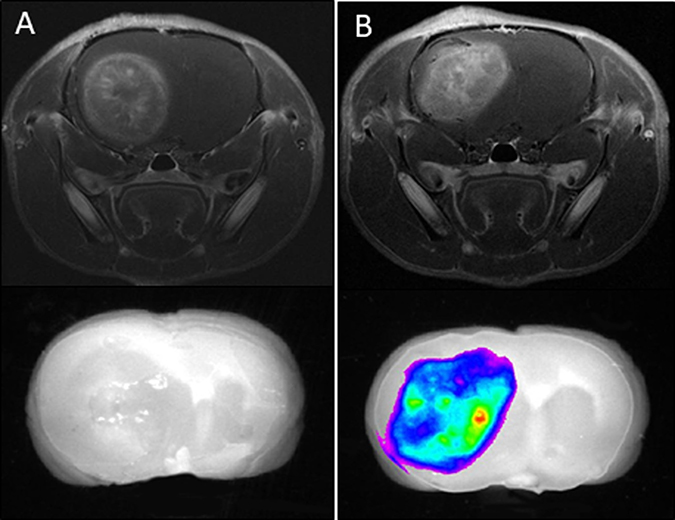

To determine the distribution of LP-iDOPE in brain tumor, Gd-enhanced MRI images and NIR images were compared. Twenty-four hours after injection, rats were sacrificed and the brains removed to obtain fluorescence images with the NIR imaging system (Figure 1). Following LP-iDOPE injection, the brain tumors showed fluorescent areas consistent with the range of the Gd-enhanced areas in MRI images. In the control animals (not injected with LP-iDOPE), the intracranial tumors showed no fluorescence.

Figure 1: Biodistribution of liposomally formulated phospholipid-conjugated indocyanine green (LP-iDOPE) in the brain. The figure shows ex-vivo near-infrared fluorescence images (lower panels) and in vivo MRI images (upper panels). (A) Non-treated rat, (B) LP-iDOPE injected rat at 24 hours after the injection. Coronal sections of the brain are shown.